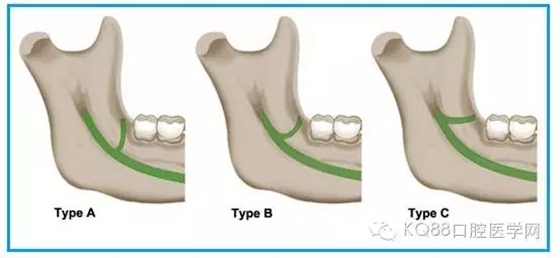

圖一 磨牙后區(qū)的形態(tài)學(xué)分類(綠色標(biāo)示):

A.水滴形;

B.細(xì)長(zhǎng)型;

C.三角形。